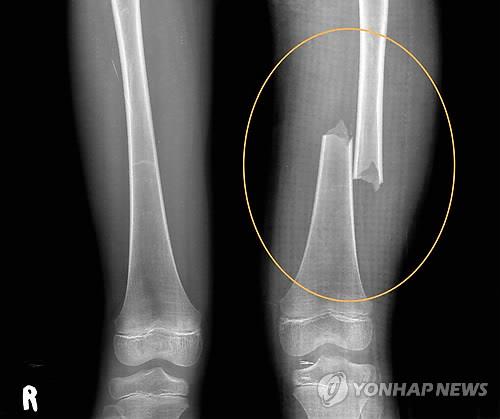

서현이는 계모인 엄마에게 5년 동안 고문보다 더한 학대를 받았다. 초등학교 1학년 때 몸에서 가장 단단하다는 허벅지 뼈가 두 동강이 났고, 같은 해 10월에는 양손과 발등, 정강이에 피부 이식 수술을 해야 하는 2도 화상을 입었다.